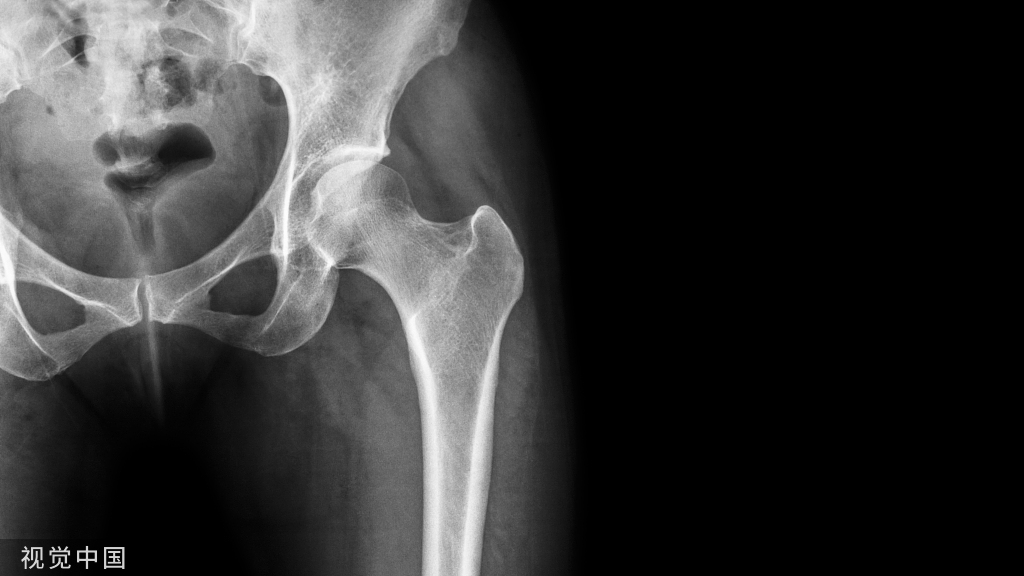

布鲁氏菌性脊柱炎早期X线表现 边缘型骨质破坏最常见,L4/L5椎体前缘呈侵蚀样骨破坏。